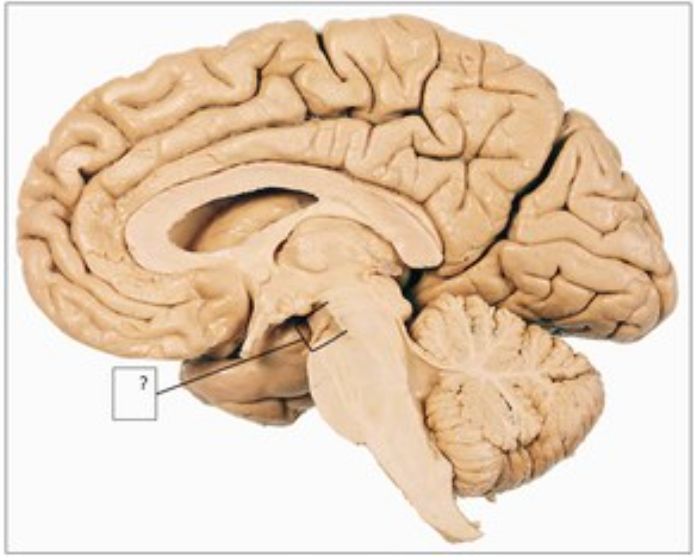

Identify “?”

midbrain